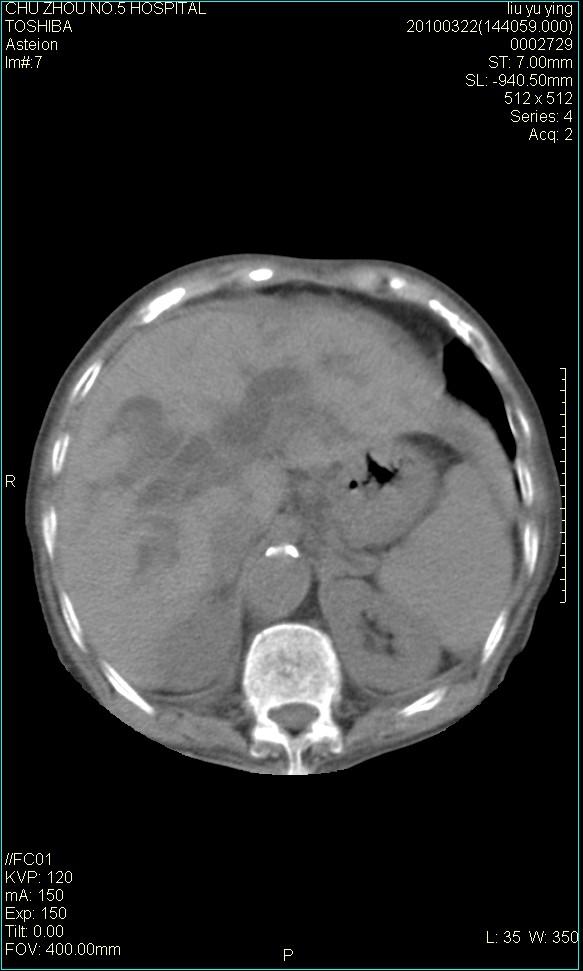

以下是引用科室第一人在2010-3-23 6:50:00的发言:[br]胆总管下段梗阻,多为肿瘤性病变,巨形胆囊,胆囊炎胆囊窝积液。[br]双侧胸腔积液,右降

以下是引用随光逐影在2010-3-23 8:12:00的发言:[br]1)胆系低位梗阻(肝内外胆管扩张,胆囊增大),原因待查。2)胆囊炎。3)双侧少量胸腔积液。4)降主动脉迂曲。